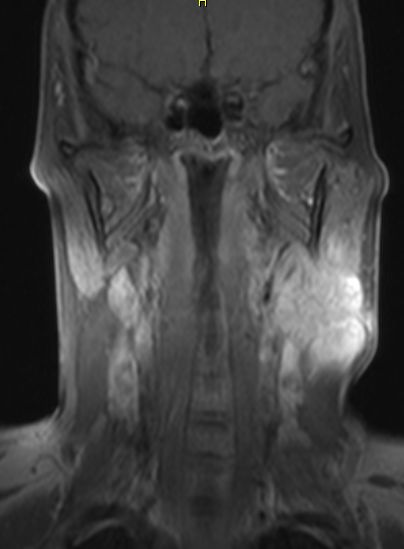

Hals-CUP 49jährige Frau mit Metastasen eines schleimbildenden Adenokarzinoms.